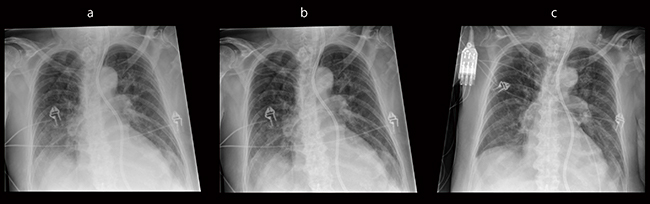

散乱線除去グリッドの落下や,X線束とのアライメントのズレによる画質劣化のリスク低減のためのソリューションとして,近年,グリッドレス撮影機構が広く一般化している。フィリップスでは,全身対応型グリッドレス撮影機構として,SkyFlow Plusを開発した。SkyFlow Plusでは,グリッド落下やアライメント不整合が招く画質劣化のリスク低減のみならず,Poetterら1)の研究によると,SkyFlowとグリッドによる画像を比較した読影試験にて,診断に適切な画質という観点から,SkyFlowは1.6倍のX線量で撮影されたグリッド使用時の画質に匹敵したと発表されており,従来のグリッドに比べ,よりX線量の適正化を図ることできる可能性が示唆されている(図4)。

図4 グリッドレス撮影機構と従来画像の比較

a:グリッドなしの画像

b:SkyFlowを適応した画像

c:グリッドを使用した画像(SKyFlow適用時の1.6倍線量での撮影)